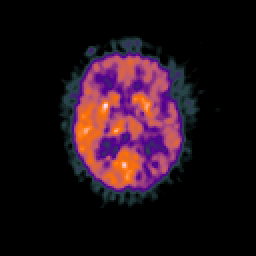

Glioma overlay -- Slice #60

[Home][Help][Clinical] Slice 60